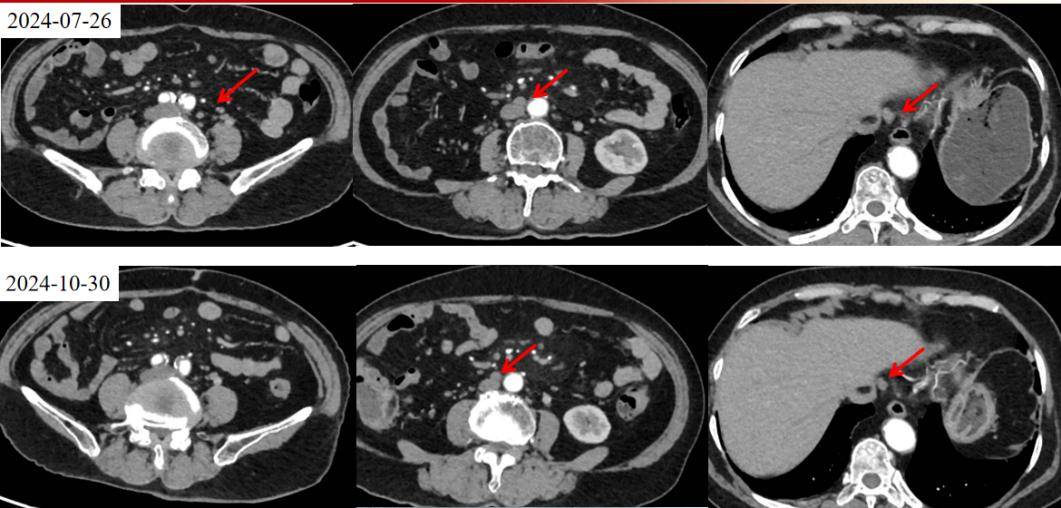

2024年7月26日胸腹部增强CT提示:直肠壁局部增厚伴强化,周围结节样淋巴结(考虑MT),肝门部及腹膜后、双侧腹股沟淋巴结。

疗效评估:2024年10月30日复查CT及MRI,影像评估提示病灶较前明显缩小(肿瘤缩小43%,盆腔淋巴结退缩),疗效评估为部分缓解(PR)。